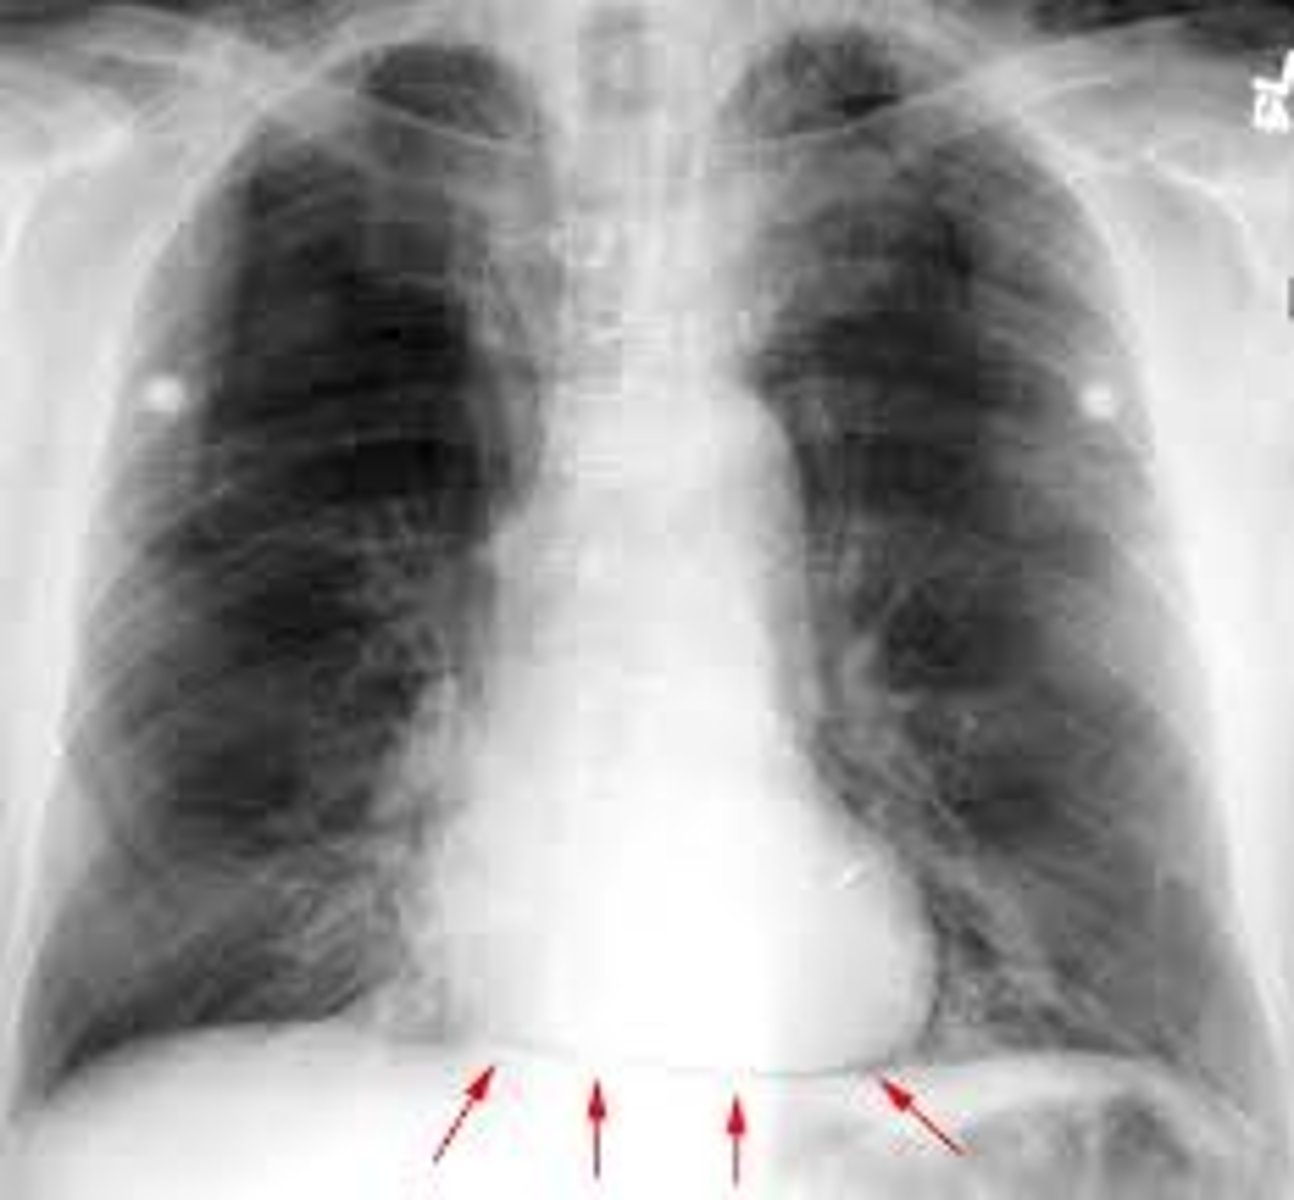

Right border of the heart

Boundary; X-ray, medial edge

L border of the heart

Boundary, X-ray, lateral edge, apex points this way

Inferior border of the heart

Boundary; X-ray, bottom edge

Superior border of the heart

Boundary; X-ray, top edge